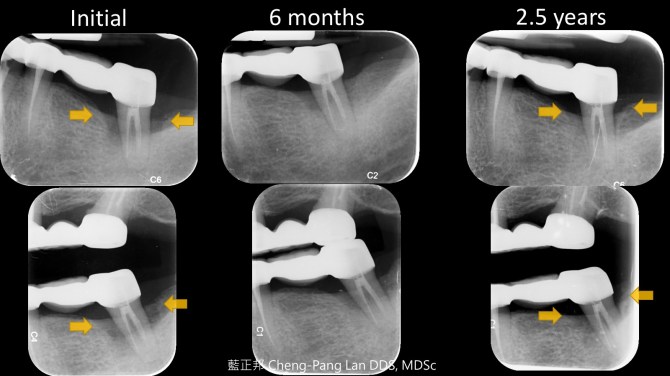

例如,36歲男性,不菸且身體健康。口腔衛生不錯,也無明顯結石與紅腫,但囊袋深及7~8mm,搖晃度頗高,隱約是一個困難案例。